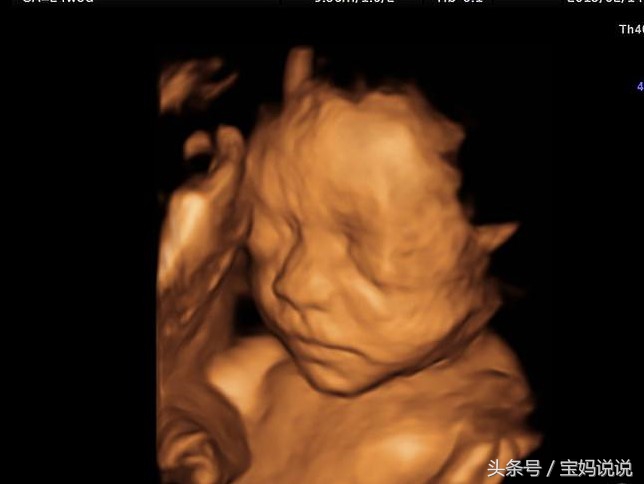

第2次:孕4-6个月的时候需要去医院做彩超检查,这个时候去做检查是可以检查胎儿的头颅、颈部、脊柱、四肢,观察胎心搏动及胎动,还有胎盘、羊水,此阶段胎儿发育观察效果 比较好。

需要提醒:很多来做彩超的孕妈妈都认为8-9个月,胎儿比较大的时候观察效果会比较好,这是错误的,因为此时胎宝宝长大,肚子的空间很有限,反而四肢颜面部会有遮挡,所以5-6个月观察四肢发育是最佳时间)

第3次:孕6.5-8.5月,这个时候去做彩超是可以检查到胎宝宝胎位,头颅,唇面部,有无脐带绕颈,脊柱、四肢、肝脏、胃、肾脏、膀胱、肠管、心脏等...尤其是要进行胎儿的心脏超声检查。还有胎盘和羊水。